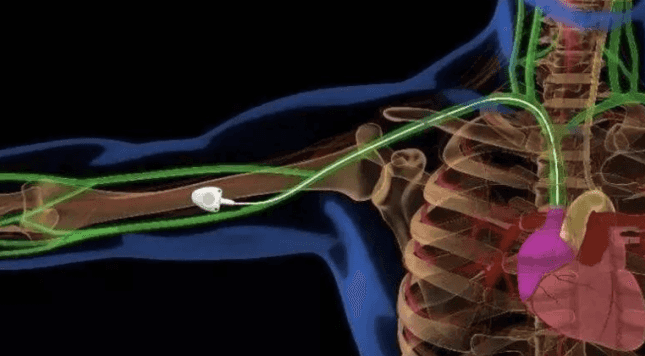

据介绍,植入式静脉输液港,又称植入式中央静脉导管系统(CVPAS),简称输液港。经手臂静脉植入式输液港是将输液港座埋置在手臂皮下的导管系统,需医、护、技人员联合完成,与目前常用的经胸壁植入式输液港相比,具有创伤小,操作难度低,输液港座位置隐秘等优点,而且手术过程简单、风险低,可避免胸壁港穿刺置管引发的血胸、气胸、导管夹闭综合症等并发症的发生。